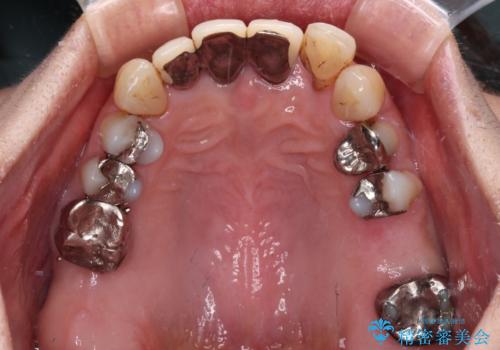

- 上顎前歯の違和感や不快感を気にして来院された患者様です。

現在のクラウンは金属の縁が見えており、歯と歯と歯肉の間に大きなスペースができていて、見た目も悪く、物が挟まったり話しにくかったりしていました。

また、前歯に抜歯が必要な歯があったため、抜歯をし、傷の治りを待ってオールセラミックブリッジにて補綴治療を行うこととしました。